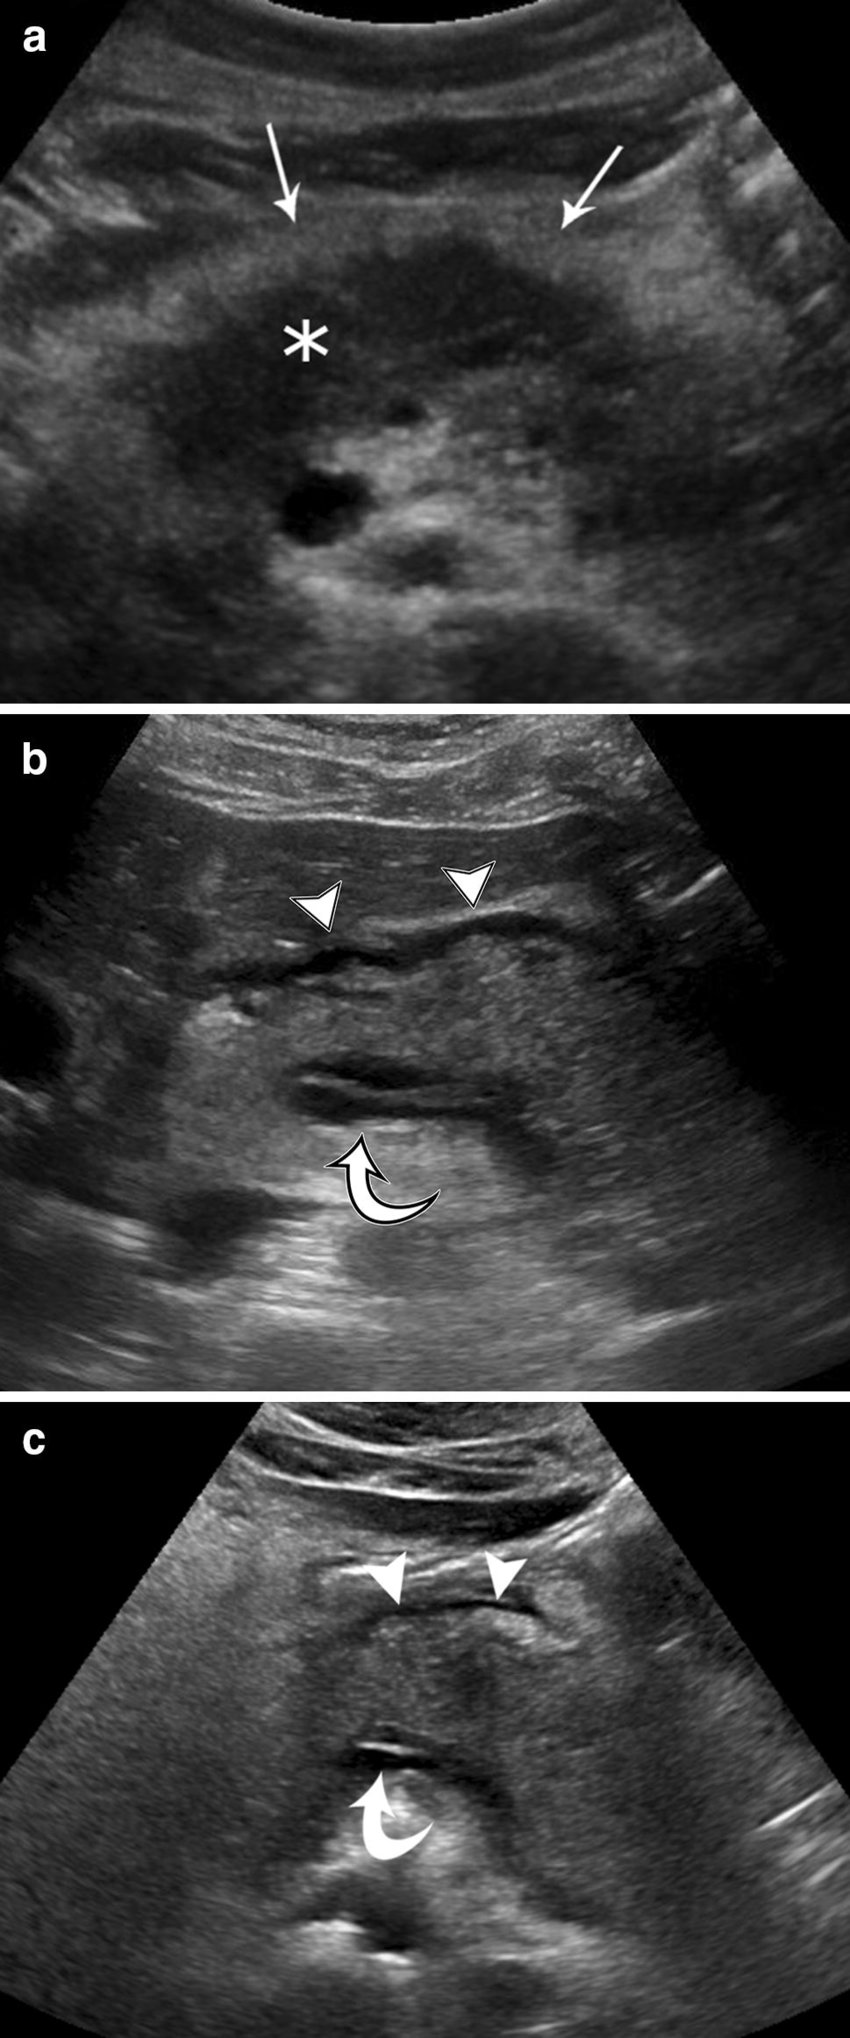

2. kép:

Akut hasnyálmirigy gyulladás (acut pancreatitis)

Ezeken a képeken több hasnyálmirigy gyulladást láthatunk. A felső (a) képen csillaggal van jelölve a hasnyálmirigy, ami kiszélesedett, echoszegény. Körülötte a nyilak oedemás zsírra mutatnak, ami szintén a gyulladás következménye.

A másik két képen is (b és c) szintén kissé echoszegényebb és kiszélesedettebb hasnyálmirigyet láthatunk amelyek körül folyadék jelent meg, ugyancsak a gyulladás következménye képpen..